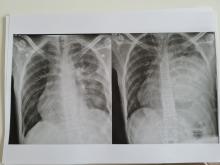

Dit is een foto van de tumor in de borstholte voor de operatie. Beiden kanten zouden hier donker grijs moeten zijn maar rechts zie je een lichte grijze bol zitten die daar niet thuis hoort. We hopen natuurlijk snel een nieuwe foto te krijgen waarop deze bol inderdaad weg is.

Na 5 maanden geleden gehoord te hebben dat er een grote tumor (17 bij 15 cm) in de borstholte zat was daar dan het moment om te proberen deze te verwijderen. Het was lange tijd erg onduidelijk of dit mogelijk was en opeens is het zover en besef je wat een risico's deze operatie met zich mee brengt. Gelukkig was Max al als eerste aan de beurt voor de operatie en omdat hij nu wist wat hij een beetje kon verwachten was hij ook wat rustiger. Patrick mocht dit keer mee naar de operatiekamer en daar ging alles vrij snel en begon voor ons het lange wachten.